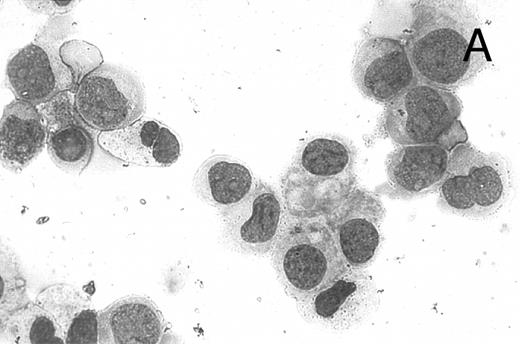

CD437 inhibition of HL-60R growth and induction of apoptosis.Although HL-60R cells are resistant to RA-mediated inhibition of growth,16,17 they are exquisitely sensitive to CD437-mediated inhibition of growth (Fig 1A) with as little as 25 nmol/L CD437 inhibiting growth by approximately 50% (Fig 1B). Similar inhibition of growth was noted in the parental HL-60 cell line (Fig 1C), as well as the RA-resistant K562 leukemia cell line28 (Fig 1D). As evidenced in Fig 1A, there was not only a total inhibition of cellular proliferation in the presence of CD437 but an actual cell loss. We therefore examined whether CD437 induced programmed cell death (apoptosis) in the HL-60R cells. That CD437 indeed induced apoptosis in the HL-60R cells was documented using three independent parameters. (A) HL-60R cells after exposure to 1 μmol/L CD437 displayed marked nuclear fragmentation and chromatin condensation, with the nuclear and cytoplasmic membranes remaining intact (Fig 2), a morphology indicative of apoptosis.29 (B) Incubation of HL-60R cells with 1 μmol/L CD437 resulted in internucleosomal cleavage and laddering of the DNA on gel electrophoresis (Fig 3), a hallmark of apoptosis.29 (C) A number of studies have suggested a critical role for cysteine proteases in the apoptotic process.30-37 Numerous substrates for this family of proteases have now been identified.37-41 PARP, which plays an important role in both DNA synthesis and repair, is cleaved early in the apoptotic process.37 38

A number of antagonists and promoters of apoptosis have recently been described. The bcl-2 family, which now consists of 7 different proteins encoded by 7 different genes, has now been characterized (Vaux and Strasser37 and the references contained within). Bcl-2 and bcl-XL are expressed in numerous cell types and are potent antagonists of apoptosis. We were unable to detect bcl-XL expression in HL-60R or HL-60 cells as has previously been described,43 but found that bcl-2 is highly expressed in these cells and is also cleaved during CD437-mediated apoptosis (Fig 6). Phosphorylation of bcl-2 has been previously described as a mechanism for bcl-2 inactivation during the apoptotic process.44 Whether cleavage of bcl-2 represents another mechanism by which bcl-2 is inactivated remains to be determined. That this cleavage of PARP, CPP32, and bcl-2 does not simply represent random cleavage of a number of proteins is suggested by our inability to detect cleavage of lamin B (data not shown), which is often found cleaved in a variety of forms of programmed cell death.39 41 CD437 also markedly inhibited growth of the K562 cells (Fig 1C) but contrary to HL-60R cells apoptosis was not noted until 144 hours of exposure to CD437, as indicated by internucleosomal degradation demonstrated by gel electrophoresis (Fig 7). We also examined the ability of CD437 to induce PARP cleavage and apoptosis in primary leukemic blasts obtained from a patient with acute myelogenous leukemia. As shown in Fig 8C, enhanced PARP cleavage was noted within 24 hours after exposure to 1 μmol/L CD437, with the apoptotic morphology noted at 48 hours of exposure (Fig 8A and B).

CD437-mediated apoptosis in primary leukemia cells. Leukemic blasts were isolated as described in the Materials and Methods. Cells were exposed to 1 μmol/L CD437 for various periods of time and PARP cleavage was assessed as previously described. (A) Leukemic cells exposed only to vehicle for 48 hours. (B) Leukemic cells exposed to 1 μmol/L CD437 for 48 hours. (C) CD437-mediated PARP cleavage. Lanes 1 and 3, cells exposed to vehicle only for 24 and 48 hours, respectively. Lanes 2 and 4, cells exposed to 1 μmol/L CD437 for 24 and 48 hours, respectively.